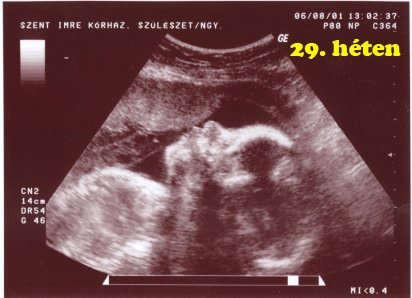

ÉLETEM LEGCSODÁLATOSABB PILLANATA MA VOLT,MERT LÁTTAM A BABÁIM SZÍVÉT DOBOGNI!

5mm-ek a picik!

Benszi, de jó hallani, hogy szívódik fel a hematoma. :) Két kis dobogó szivecske. :) Gondolom milyen boldogság öntött el. :) UH kép nincs? :)